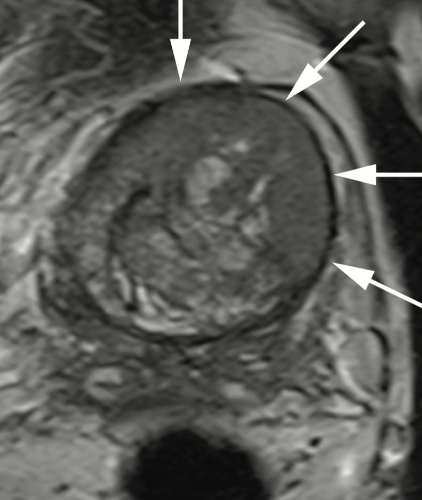

A PI-RADS 5 lesion was identified in the left anterior TZ (Figures 1A-1D), and an 18-core TRUS fusion biopsy shortly thereafter revealed 2 cores of Gleason 3 + 4 = 7, Gleason grade (GG) 2 disease (Figure 2A). After metastatic staging with a negative CT and nuclear medicine bone scan, he underwent open radical prostatectomy (RP) in May 2021. Final pathology revealed a 66-gram prostate, Gleason 4 + 3 = 7, GG3, organ-confined disease with negative lymph nodes, pT2N0Mx (Figure 2B).

A: Prostate MRI is a challenging imaging study to interpret, especially in the TZ. The TZ is challenging because of the overlap in imaging appearance of certain types of benign prostatic hyperplasia nodules with malignancy. Specifically, the degree of restricted diffusion and contrast enhancement can overlap with stromal and hyperplastic nodules, respectively. That said, there are morphologic features of anterior TZ lesions that are critical to recognize. Specifically, T2 weighted imaging is the dominant imaging sequence used to diagnose and characterize TZ lesions and these are characterized by an "erased charcoal" appearance, as in this case. Also, these lesions should have markedly restricted diffusion as evidenced by low signal on apparent diffusion coefficient (ADC) maps and high signal on high b-value diffusion weighted imaging (DWI).